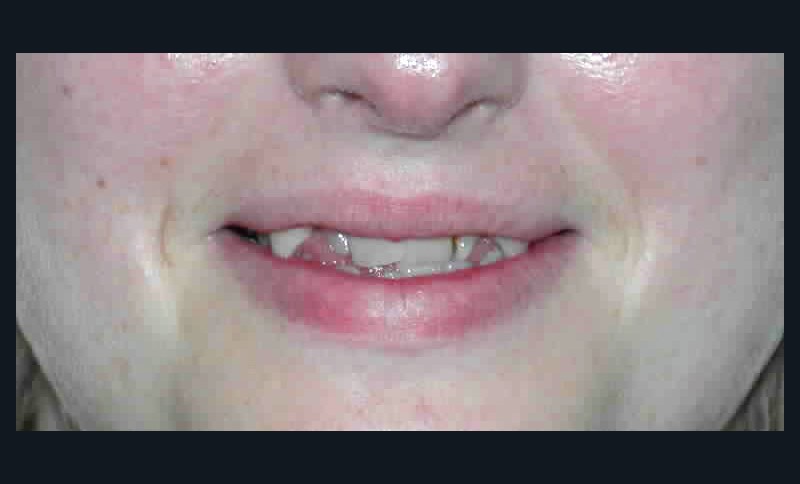

Le sourire est inesthétique (fig. 3) et de profil il existe une rétrochéilie supérieure (fig. 2).